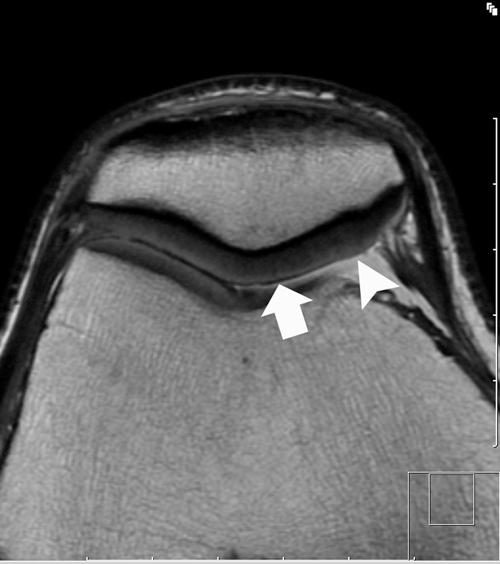

Although disorders of the patellofemoral joint are common in the athlete, their management can be challenging and require a thorough physical examination and radiologic evaluation, including advanced magnetic resonance imaging techniques.

Physical examination and imaging evaluation including standard radiographs are crucial in identifying evidence of malalignment or instability. Magnetic resonance imaging provides valuable information about concomitant soft tissue injuries to the medial stabilizers as well as injuries to the articular cartilage, including chondral shears and osteochondral fractures. Quantitative magnetic resonance imaging assessing the ultrastructure of cartilage has shown high correlation with histology and may be useful for timing surgery.

Evaluation of patellofemoral disorders is complex and requires a comprehensive assessment. Recent advancements in imaging have made possible a more precise evaluation of the individual anatomy of the patient, addressing issues of malalignment, instability, and underlying cartilage damage.